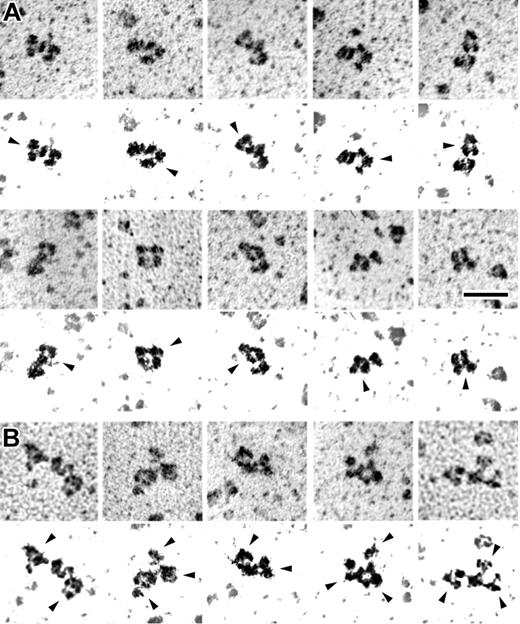

Next, PF4-heparin complexes were rotary shadowed and examined by electron microscopy. The complexes studied were prepared at a PF4-heparin ratio where only ULCs were expected to form (Figure 1C). As seen in Figure 3, electron microscopy showed an even distribution of particle size. The structures observed in these experiments were quite uniform in appearance and mostly globular in form, although they were commonly somewhat longer in 1 direction than in the other, with mean size of 7.5 ± 0.4 nm × 13.5 ± 2.0 nm. These dimensions are consistent with the SEC data and support a molecular weight of 650 kDa or greater. Although some of the particles had apparent substructure, the appearance was not consistent enough for more definitive identification.

Transmission electron microscopy of rotary shadowed PF4-heparin complexes. Fields demonstrating the appearance of PF4-heparin complexes at the optimal PF4-heparin ratio. Triangles (▸) indicate representative ULCs; arrows point to representative SCs. The coating of metal from the shadowing technique makes the extended structure of the IgG appear artificially larger in comparison to that of compact structure of the PF4-heparin complexes. Magnification bar = 50 nm.

KKO is a monoclonal antibody that mimics a subset of HITT antibodies27 and that causes heparin-induced thrombocytopenia and thrombosis in a murine model.11 The ability of KKO to recognize the various PF4-heparin complexes was tested by using a capture ELISA. Wells were precoated with KKO or with monoclonal or polyclonal anti-PF4 and equal amounts by weight of PF4 from each of the 3 major fractions were added. As shown in Figure 5, KKO preferentially captures ULCs. Binding of the antibody to ULCs was verified by immunoelectron microscopy (Figure 6). Although antibodies are flexible structures, their 3-lobed structures were often seen binding to the PF4-heparin complexes (Figure 6A). In addition, numerous examples were visualized where there were 2 or more antibodies binding to 1 PF4-heparin complex (Figure 6B).

Transmission electron microscopy of rotary shadowed PF4-heparin complexes with KKO antibody bound. Galleries showing the appearance of PF4-heparin complexes with KKO antibody bound. IgG molecules have a typical 3-lobed structure, but their appearance can vary widely because they are quite flexible molecules. (A) Examples of PF4-heparin complexes with a single KKO bound. (B) Examples of PF4-heparin complexes with multiple KKO antibodies bound to each. Below each frame is very high contrast image to highlight the shadowed molecules and eliminate the background. Arrows point to the antibodies. Magnification bar = 50 nm. Adobe Photoshop 7.0 (Adobe, San Jose, CA) was used to produce high-contrast images.